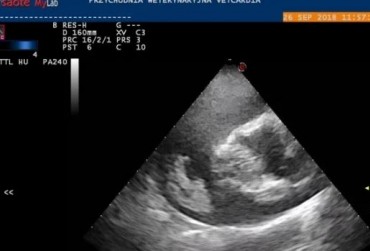

Echo serca z widoczną obecnością dużej liczby nicieni w prawym przedsionku serca (1)

16 kwietnia 2019

Wojciech Atamaniuk

Czytaj więcej